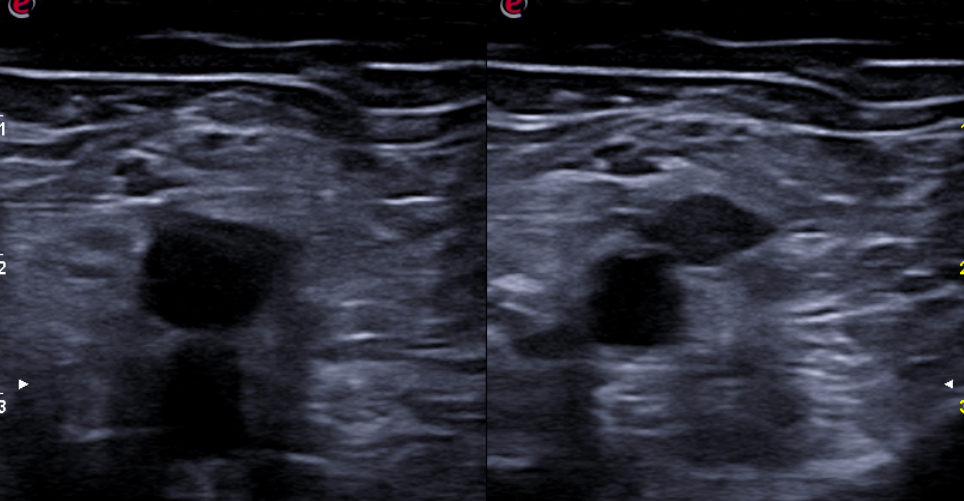

Expondremos la utilidad de la EC como herramienta en el manejo de los pacientes con diferentes tipos de dolor que atiende el Médico de Familia en las consultas diarias, urgentes, e incluso en los domicilios, en diversos escenarios clínicos a los que podemos enfrentarnos en nuestra práctica clínica habitual, desde un dolor visceral (abdominal, torácico, urológico o ginecológico), un dolor músculo-esquelético (traumático o no, con sospecha de fractura u osteoartrósico incapacitante), un dolor vascular (sospecha de trombosis venosa profunda, trombosis arterial aguda, aneurismático); ayudando a obtener una información crucial con un método no invasivo que nos ayudará a reducir la incertidumbre y orientar mejor el diagnóstico de nuestros pacientes e incluso nos podrá ser muy útil como herramienta con fines terapéuticos como en el caso de las infiltraciones ecoguiadas.

En nuestra experiencia como Centro de Salud que utiliza de forma rutinaria la Ecografía clínica, hemos visto un importante avance en nuestra capacidad resolutiva en muchos casos, mejorando el diagnóstico diferencial de los diferentes tipos de dolor, su abordaje terapéutico precoz, e incluso ayudando a los pacientes a una mejor comprensión de su patología.

Consideramos la Ecografía clínica como una herramienta de gran utilidad en la consulta de Atención Primaria, que puede aportar gran ayuda al Médico de Familia en la toma de decisiones, ayudando a obtener diagnósticos diferenciales precoces y que también ayuda a agilizar las derivaciones pertinentes al conseguir en muchos casos un enfoque diagnóstico más preciso.